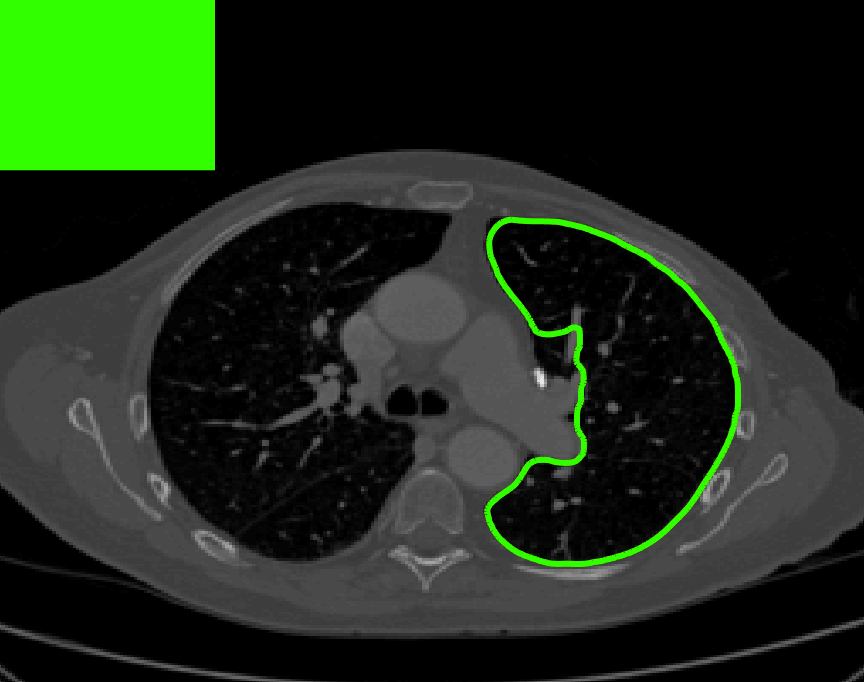

The motivation for this work comes from observing contradictions in using piecewise-constant intensity fitting terms in selective segmentation. Whilst good results are possible with this approach, the exceptional cases lead to severe limitations in practice. This is quite common in medical imaging as demonstrated in Fig. 1, where the target foreground has a low intensity. Given that the corresponding background includes large regions of low intensity, the optimal average intensities for this segmentation problem are and . For cases where , we see that by (1), almost everywhere in the domain . This means that it is very difficult to achieve an adequate result, without an over-reliance on the user input or parameter selection.

where is noise, is the characteristic function of the region , for respectively. The idea of selective segmentation is to incorporate user input to apply constraints that exclude regions classified as foreground, based on their location in the image. We use a distance constraint which penalises the distance from the user input markers. However, a key problem for selective segmentation is that for cases where the optimal intensity values and are similar, the intensity fitting term will become obsolete as the contour evolves. This is illustrated in Fig. 3. The purpose of our approach is to construct a model that is based on assumptions that are consistent with the observed image and any homogeneous target region of interest. A common approach in selective segmentation is to discriminate between objects of a similar intensity Rada:13 ; Geo ; CDSS . However, the fitting terms in previous formulations Klodt:13 ; Rada:13 ; Geo ; CDSS aren’t applicable in many cases as there are contradictions in the formulation in this context. We will address this in detail in the following section.

[\capbeside\thisfloatsetupcapbesideposition=left,top,capbesidewidth=1.5in]figure[\FBwidth]

for and as defined in (33). This is consistent with respect to the intensities of the observed object and the concept of selective segmentation. In Fig. 3 we see the difference between CV and the proposed fitting terms for given user input on a CT image. For the CT image, the CV fitting terms are near 0 within the target region. This is despite there being a distinct homogeneous area with good contrast on the boundary. This illustrates the problem we are aiming to overcome. With the proposed fitting term this phenomenon should be avoided in cases like this. By defining as in (33) there is no contradiction if the foreground and background intensities of the target region are similar.